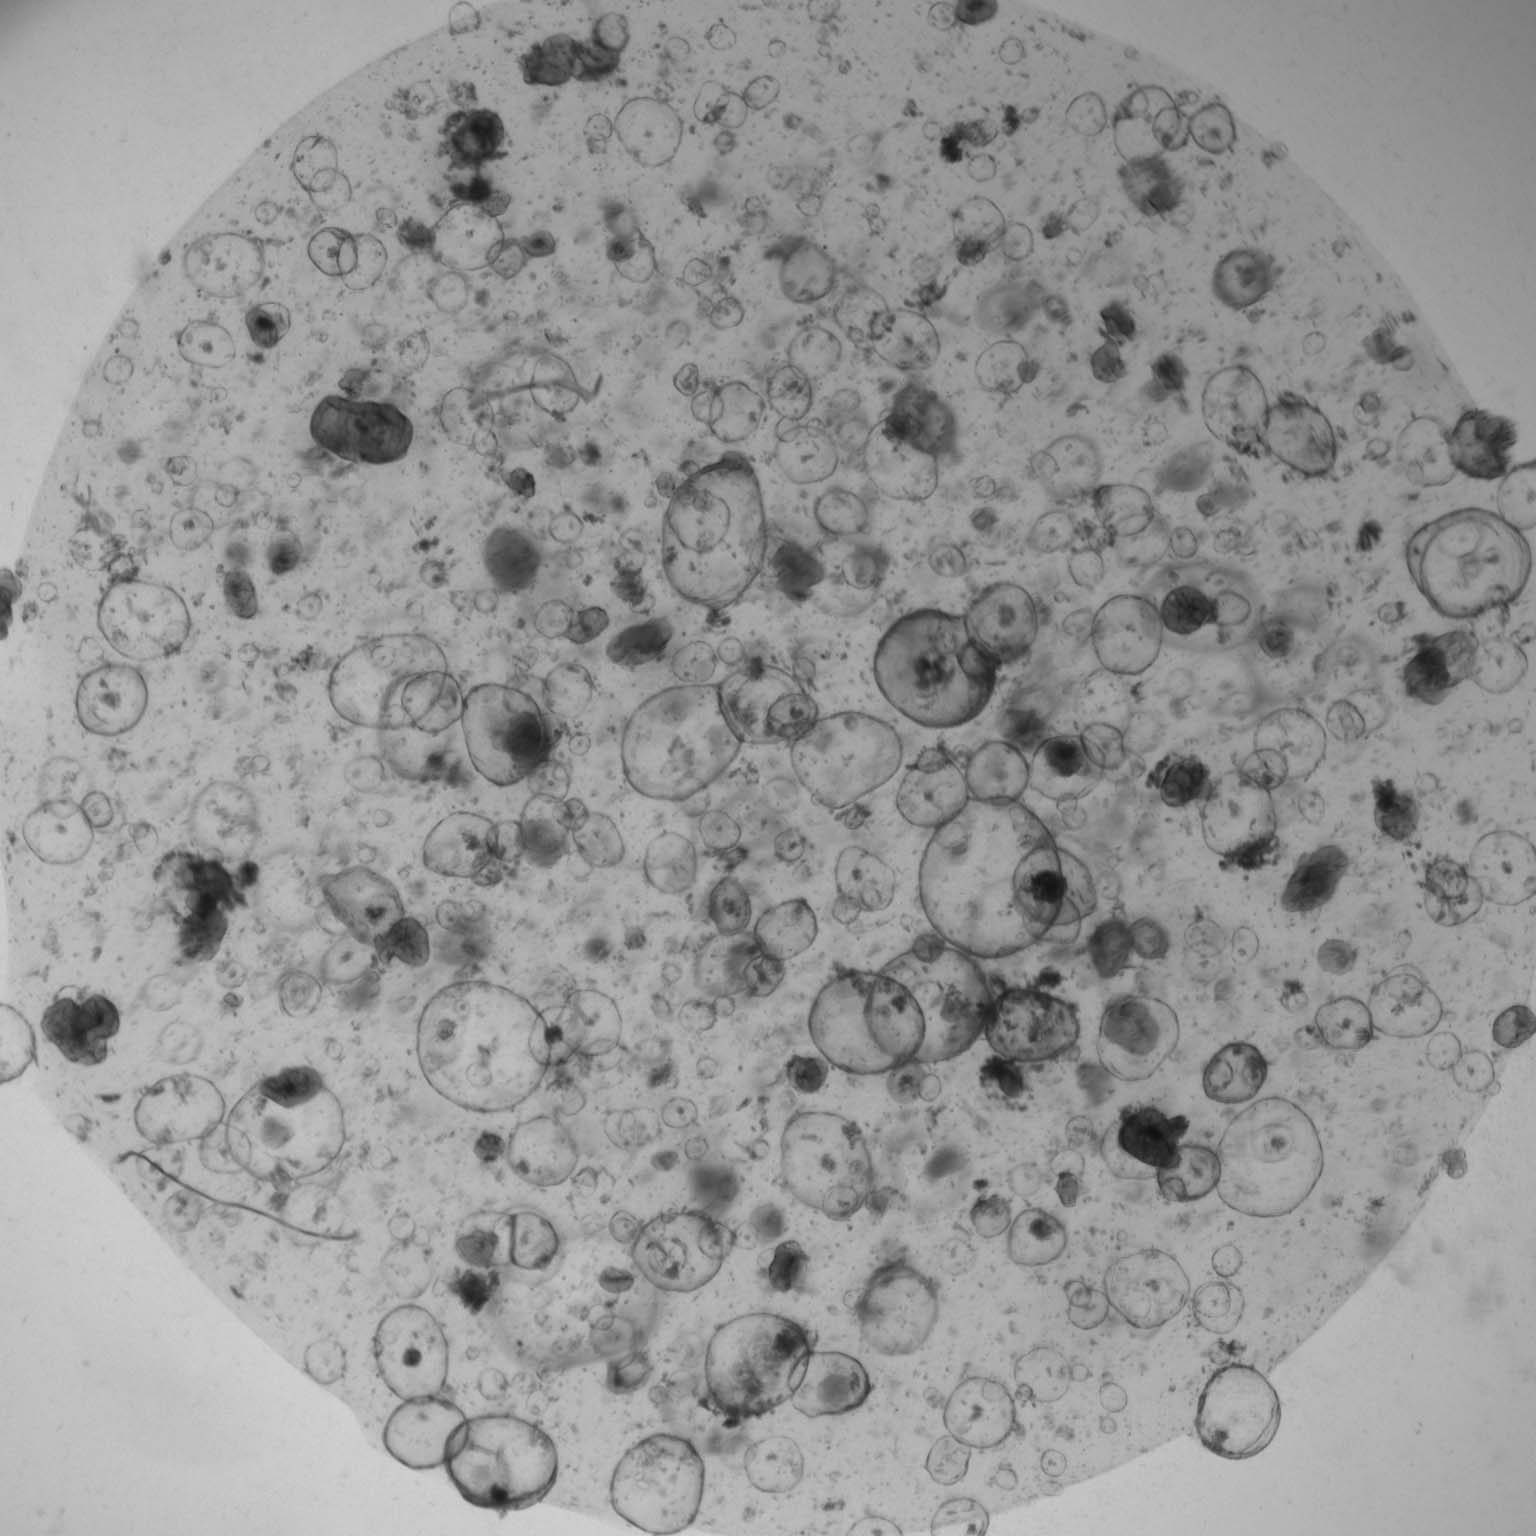

We seek to understand colorectal cancer across the spectrum from normal, to pre-malignancy, early cancer, and metastatic disease.